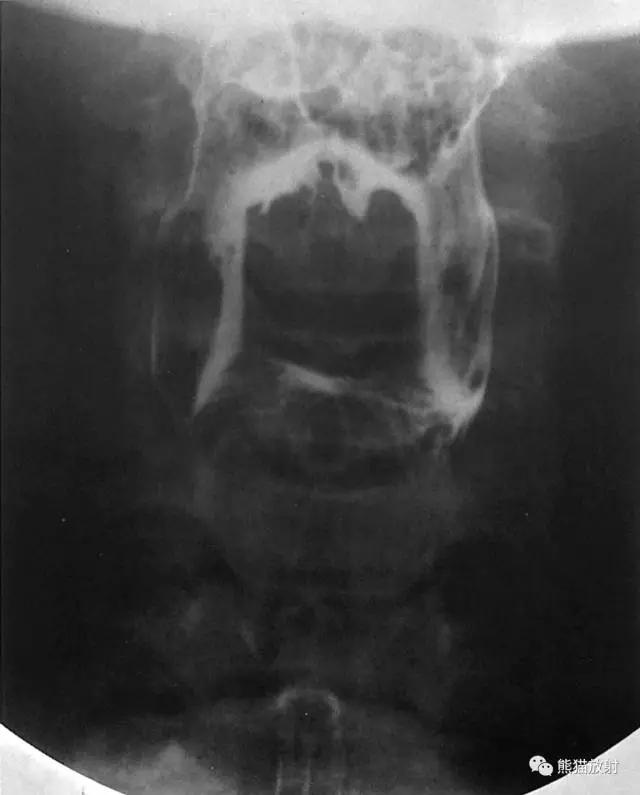

1 Anterior-Posterior View of the Hypopharynx 下咽部( 前后位 )

1 Pharynx 咽腔,2 Lateral glossoepiglottic fold 舌会厌外侧襞,3 Vallecula 会厌谷,4 Epiglottis 会厌,5 Piriform recess 梨状隐窝,6 Esophagus 食管